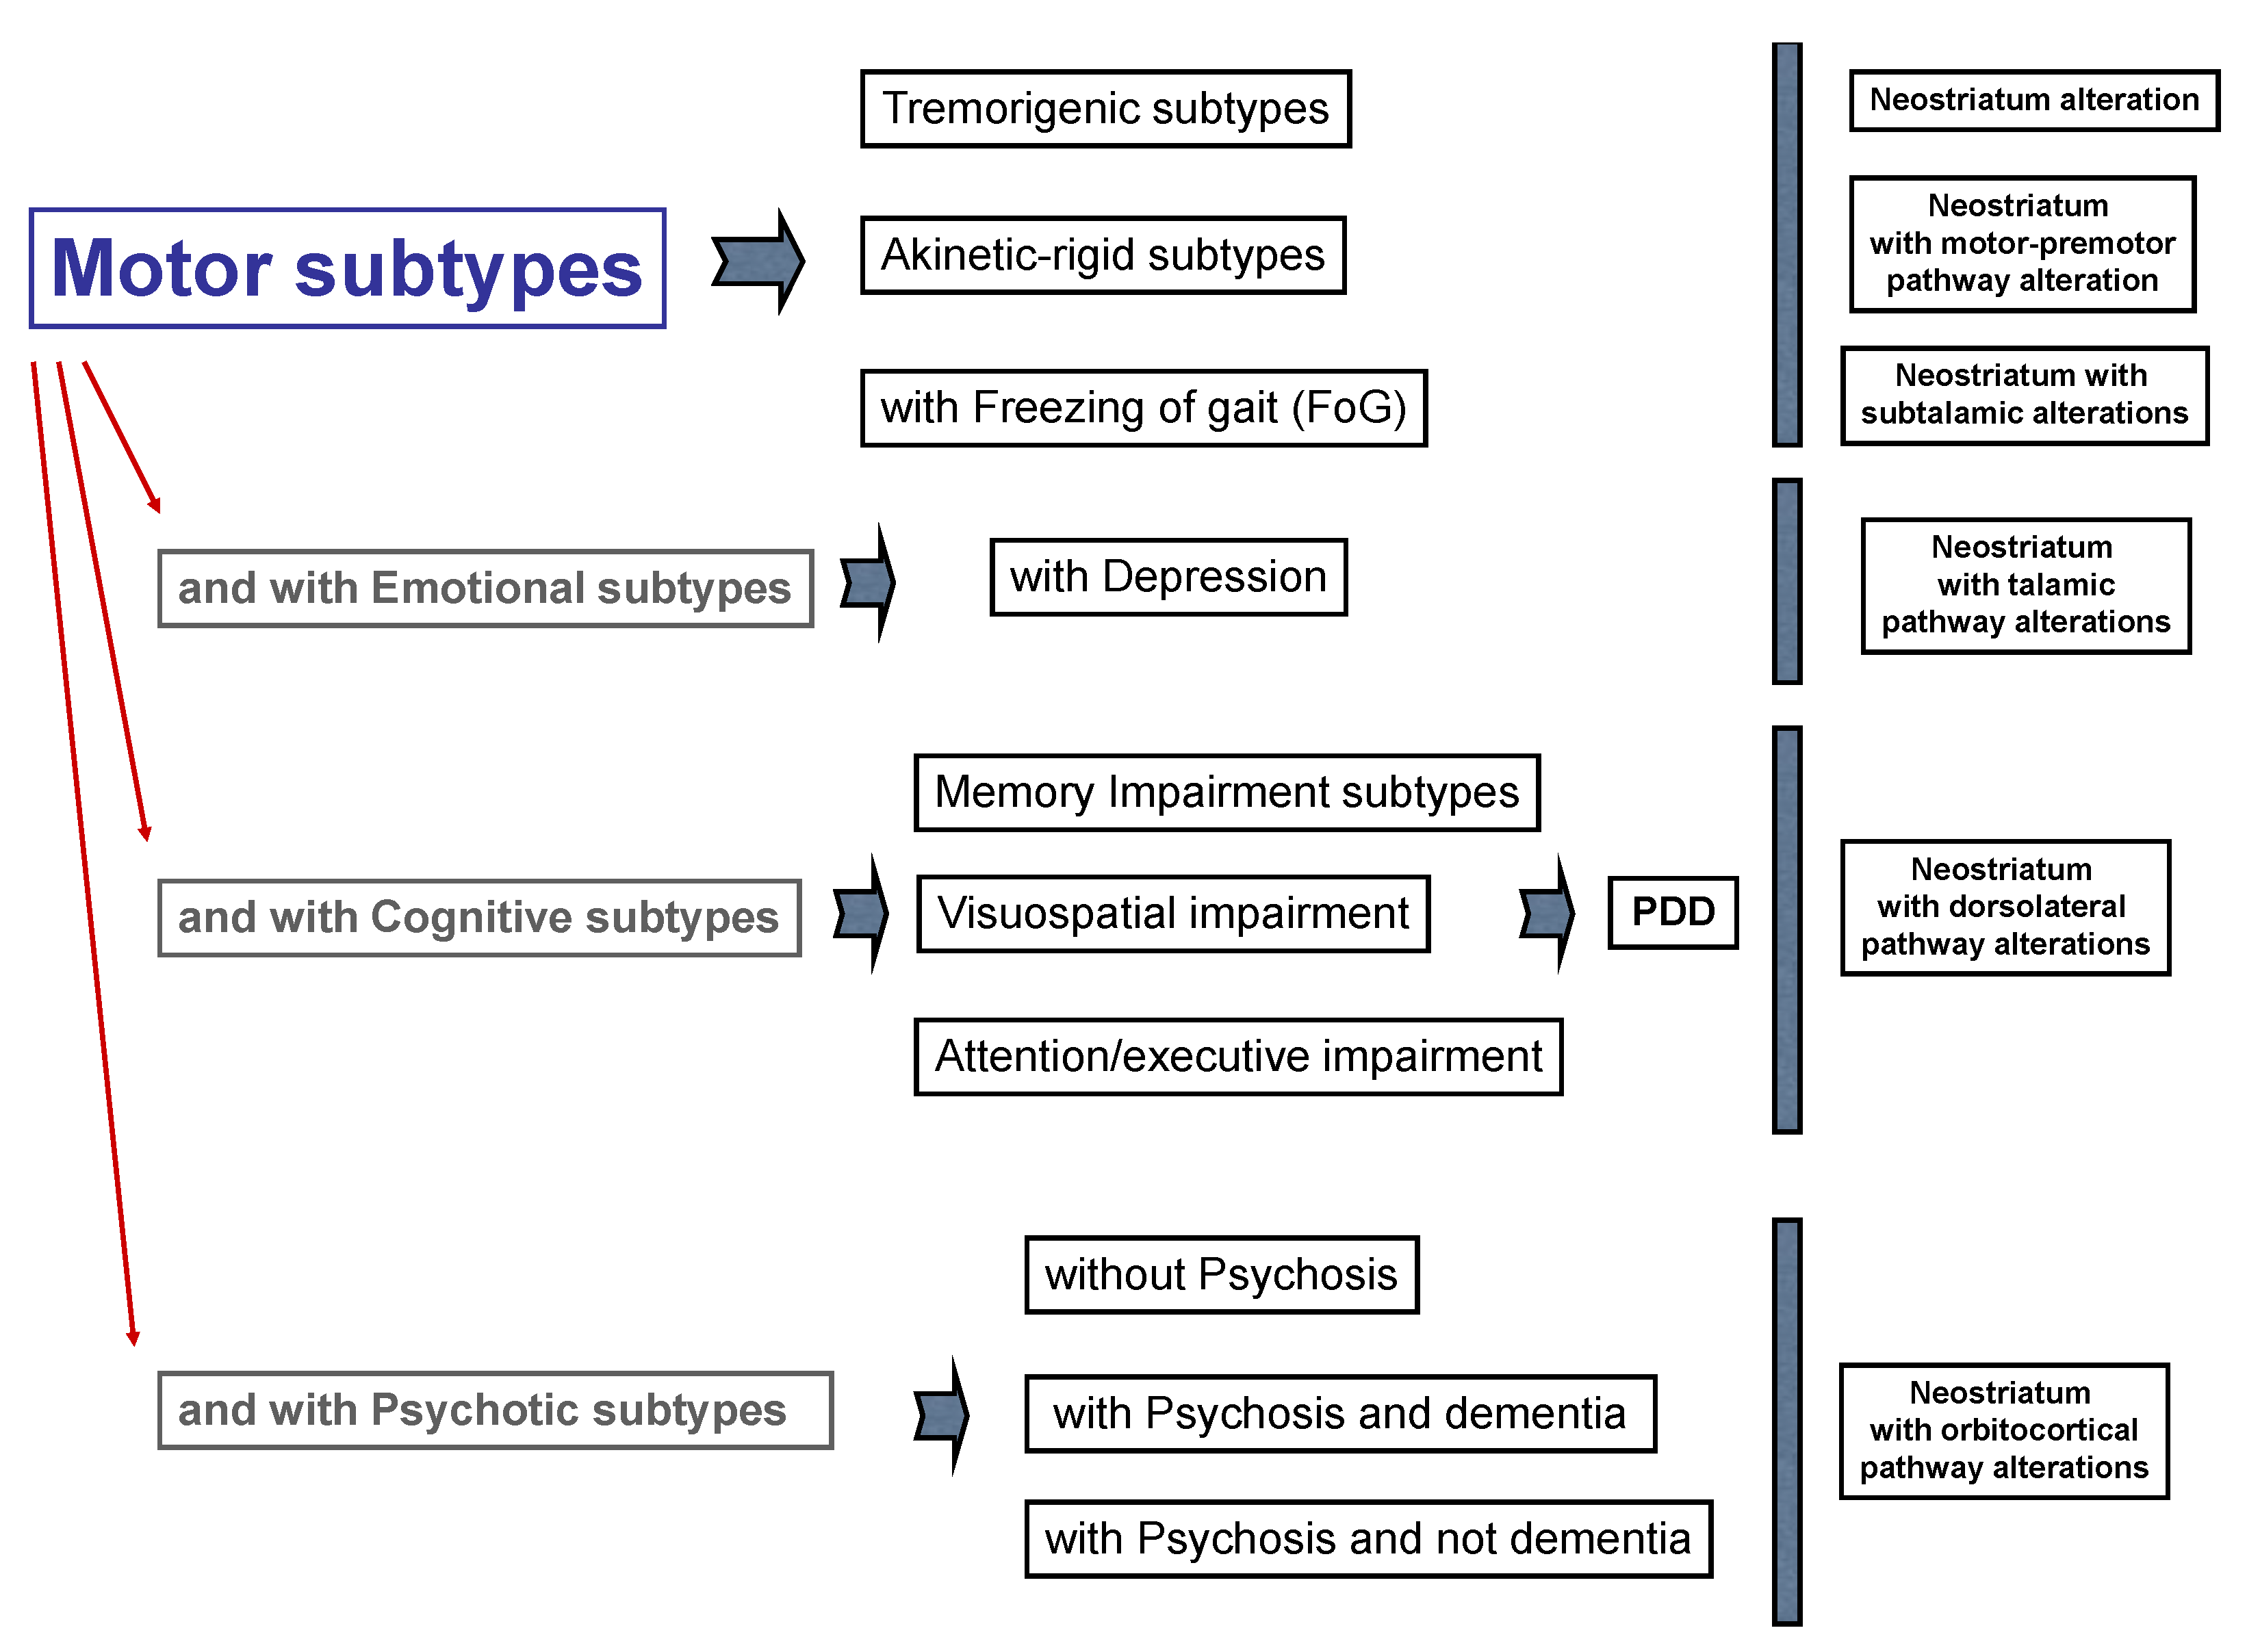

3. Parkinson’s Disease Subtypes Identified by Tractography

- Lauretani, F.; Saginario, A.; Ceda, G.P.; Galuppo, L.; Ruffini, L.; Nardelli, A.; Maggio, M. Treatment of the motor and non-motor symptoms in Parkinson’s disease according to cluster symptoms presentation. Curr. Drug Targets 2014, 15, 943–947. [Google Scholar] [CrossRef] [PubMed]

- Erro, R.; Vitale, C.; Amboni, M.; Picillo, M.; Moccia, M.; Longo, K.; Santangelo, G.; De Rosa, A.; Allocca, R.; Giordano, F.; et al. The heterogeneity of early Parkinson’s disease: A cluster analysis on newly diagnosed untreated patients. PLoS ONE 2013, 8, e70244. [Google Scholar] [CrossRef] [PubMed]

- Belvisi, D.; Fabbrini, A.; De Bartolo, M.I.; Costanzo, M.; Manzo, N.; Fabbrini, G.; Defazio, G.; Conte, A.; Berardelli, A. The Pathophysiological Correlates of Parkinson’s Disease Clinical Subtypes. Mov. Disord. 2021, 36, 370–379. [Google Scholar] [CrossRef]